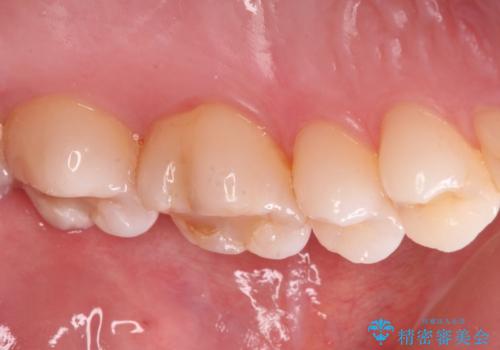

- 昔他院で虫歯治療をしたところが虫歯が再発したとのことで来院。

古い材料(プラスチックの樹脂)をとり、拡大鏡下で虫歯を全て取り除き、

ゴールドインレーにて治療しました。

歯の外側の面が少し欠けていて、そこの部分を覆う(ゴールドの範囲が広くなる)か

そこの欠けてる部分は虫歯ではないので削らないで、最小限にして詰め物を作るか相談したところ

欠けているところは何十年も昔から欠けていて特に何もない。なるべく歯を削りたくないとの事だったので

最小限で詰め物の治療をしました。